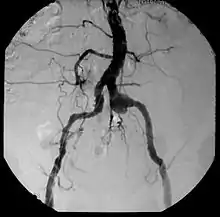

| Aneurysm, a commonly lethal complication of SA | |

| Complications | Aneurysm |

Syphilitic aortitis is inflammation of the aorta associated with the tertiary stage of syphilis infection. SA begins as inflammation of the outermost layer of the blood vessel, including the blood vessels that supply the aorta itself with blood, the vasa vasorum.[3] As SA worsens, the vasa vasorum undergo hyperplastic thickening of their walls thereby restricting blood flow and causing ischemia of the outer two-thirds of the aortic wall. Starved for oxygen and nutrients, elastic fibers become patchy and smooth muscle cells die. If the disease progresses, syphilitic aortitis leads to an aortic aneurysm. Overall, tertiary syphilis is a rare cause of aortic aneurysms.[3] Syphilitic aortitis has become rare in the developed world with the advent of penicillin treatments after World War II.

Inflammatory involvement of tertiary syphilis begins at the adventitia of the aortic arch which progressively causes obliterative endarteritis of the vasa vasorum.[3] This leads to narrowing of the lumen of the vasa vasorum, causing ischemic injury of the medial aortic arch and then finally loss of elastic support and dilation of the vessel.[3] Dissection of the aortic arch is rare due to medial scarring. As a result of this advanced disease process, normal methods of angiography/angioplasty may be impossible for those with suspected coronary artery disease.